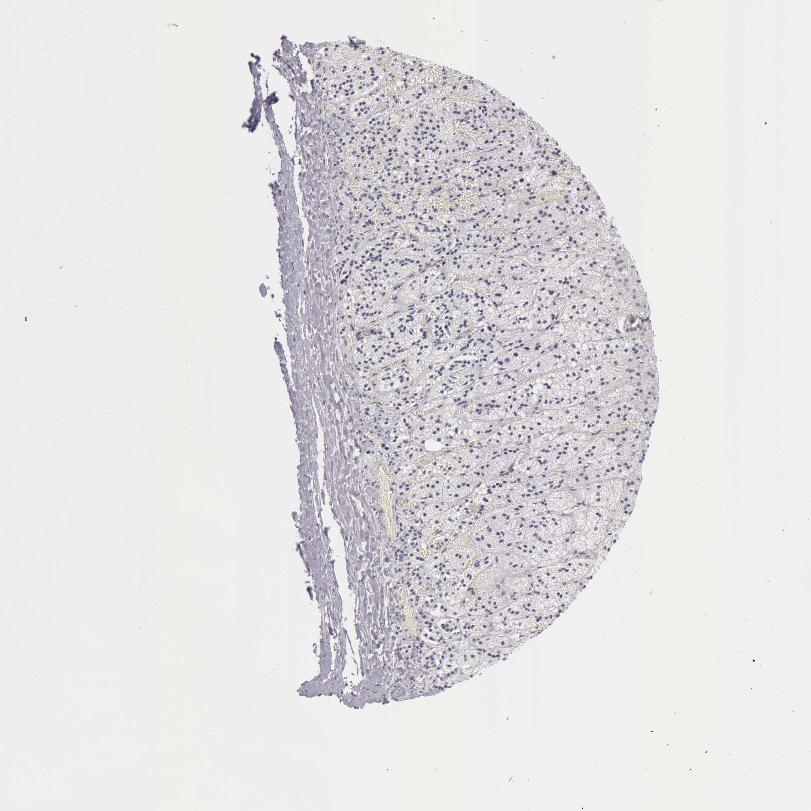

TISSUE PRIMARY DATA ADRENAL GLAND Show tissue menu

ADRENAL GLAND - Antibody stainingi

Antibody staining in the annotated cell types in the current human tissue is reported as not detected, low, medium, or high, based on conventional immunohistochemistry profiling in selected tissues. This score is based on the combination of the staining intensity and fraction of stained cells.

Each image is clickable and will lead to virtual microscopy that enables deeper exploration of all samples and also displays staining intensity scores, fraction scores and subcellular localization as well as patient and tissue information for each sample.

Antibody HPA019527Antibody HPA020912Antibody CAB001809

Glandular cells MediumLowNot detected